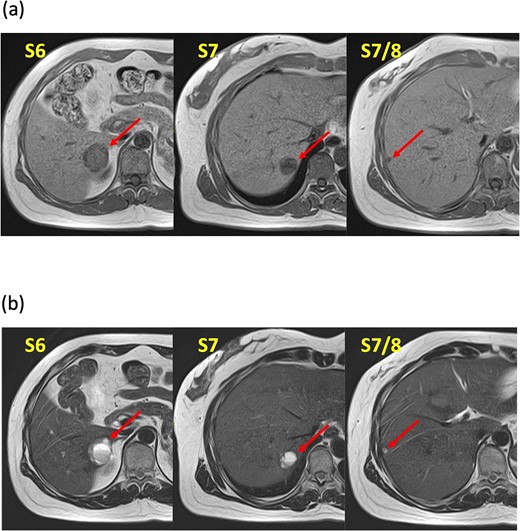

A 52-year-old woman was admitted to our hospital for the evaluation and treatment of multiple cystic liver tumors. Two years earlier, dynamic computed tomography (CT) had detected multiple cystic tumors in segments 6 (S6) and 7 (S7), which were subsequently monitored (Fig. 1a). The patient showed no symptoms; laboratory tests for tumor markers such as α-fetoprotein, protein induced by vitamin K absence or antagonist-II, carcinoembryonic antigen, and carbohydrate antigen 19–9 were within normal ranges. Dynamic CT identified two low-density tumors with peripheral enhancement in the portal phase, featuring cyst-like internal septa (Fig. 1b), which showed slow enlargement over 2 years. Magnetic resonance imaging (MRI) using gadoxetic acid (gadolinium-ethoxybenzyl-diethylenetriamine pentaacetic acid; EOB Primovist®) revealed that tumors appeared as low intensity signals on T1-weighted imaging and high intensity signals on T2-weighted imaging and diffusion-weighted imaging. Additionally, a 7-mm lesion was observed at the S7/8 boundary (Fig. 2a and b). Positron emission tomography-CT (PET-CT) showed abnormal uptake in S6 and S7 tumors but not in the S7/8 lesion (Fig. 3). CT during hepatic arteriography (CTHA) demonstrated well-contrasted tumors at the periphery, with no contrast enhancement in the center (Fig. 4a). Moreover, CTHA detected a new tumor in S8, displaying clear and uniform contrast but not visible with other imaging modalities (Fig. 4b).

Magnetic resonance imaging findings. Known tumors are visible in S6, S7, and an additional tumor is found at the S7/8 boundary. These tumors appeared as low-intensity lesions on (a) T1-weighted images and (b) high-intensity lesions on T2-weighted images.